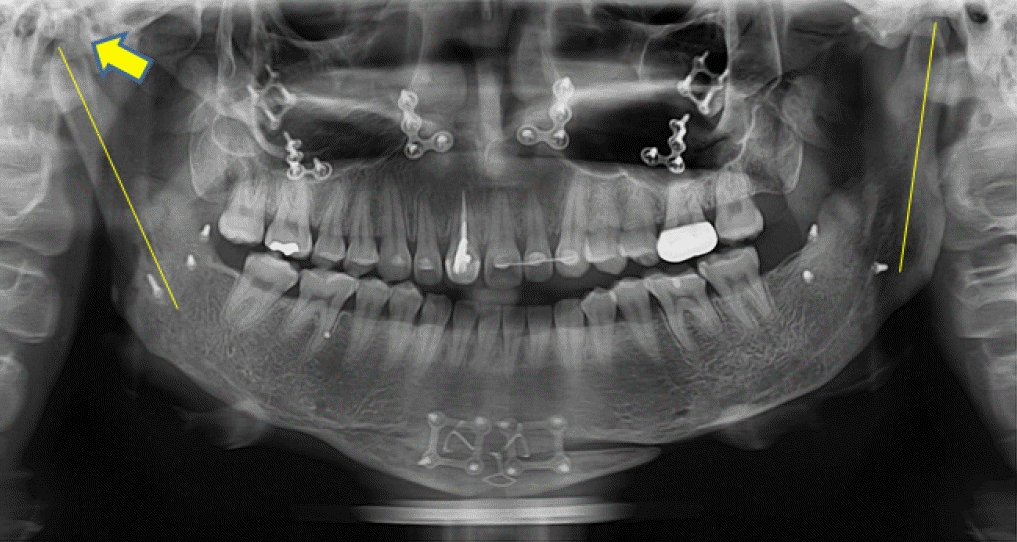

28세 여성이 안면비대칭과 턱관절의 불편감으로 내원하였다. 안모는 우측으로 비대칭이 관찰되었으며, 우측 턱관절부위의 관절잡음이 있었으며 26mm 개구 시 과두걸림이 있었다. 최대개구량은 48mm이고 우측으로 변위된 개구 양상을 보였다. 안면 CT와 X-ray 촬영 결과, 좌측 하악지가 우측 하악지에 비해 12.89mm 길었으며 관절까지의 방향이 우측 하악지에 비해 외측으로 향해 있는 것을 알 수 있었다(Fig. 1). 우측 하악체의 길이가 좌측에 비해 길고 이로 인해 하악 턱끝은 정중선에 비해 우측으로 13.8mm 편위되어 있었다. 그리고 교합평면은 좌측으로 기울어지고 구치부 반대교합과 전치부 절단교합이 존재하였다(Fig. 2). 안면비대칭과 턱관절원판의 정복성 전방변위로 진단하고 하악골의 비대칭과 교합평면의 개선을 위해 턱교정수술과 치아교정술을 계획하였다. 턱교정수술은 상악골 후상방(좌측: 3.5mm, 우측: 4.5mm)이동하고, 하악골은 후방(좌측: 17.5mm, 우측: 5.5mm) 이동하였다(Fig. 3). 턱끝성형술과 하악골 윤곽성형술을 통해 하악골과 안모의 대칭에 도움을 주었다. 하악골수술은 시 시상분할절골술을 이용하였으며, 관절과두가 포함된 근심골편을 재위치시켜주어 과두걸림을 해소하려 하였다. 수술 2주후 치아교정술을 시작하면서 개구연습을 진행하였으며 비대칭적 개구 습관의 교정을 위해 탄성고무줄을 이용하여 중심선에 맞게 진행하였다. 수술 6개월 후 평가 시, 안모의 비대칭은 개선된 결과를 보였으며(Fig. 4) 턱관절 부위의 과두걸림은 관찰되지 않고 정상범위 내의 개구 양상을 보였다.- 증례 2

32세 여성이 우측 턱관절의 통증과 개구제한을 주소로 내원하였다. 내원 전에 3차례에 걸쳐 각각 다른 의료기관에서 턱교정수술을 받은 경험이 있고, 음식물 저작이 힘들고 입이 비뚤어져 사회관계에도 문제가 있었다. 안모는 좌측으로 변위된 비대칭이 관찰되었고 교합은 상악골의 우측 변위, 하악골의 경사진 좌측 변위로 인해 치아 중심선 비대칭을 포함하여 전치부의 개방교합과 구치부의 반대교합이 관찰되었다(Fig. 5). 우측 관절부위 통증과 다수의 수술로 인한 저작근 주위 조직의 경직으로 인해 자발적 최대개구량은 23mm이었다. 파노라마방사선영상에서 우측 하악과두가 좌측에 비해 glenoid fossa으로 부터 떨어져 있고 전방으로 기울어져 있는 것을 관찰할 수 있었다(Fig. 6). 이전 하악골편 고정시 하악과두가 포함된 근심골편이 후방으로 위치하여 고정된 것과 상악골의 우측 변위되어 고정된 것을 개선시키기 위해 4번째 턱교정재수술(4th reoperation)과 치아교정술을 계획하였다. 상악골의 수술 시 하악골의 안정을 위해 후상방이동 2.5mm와 기울어진 교합평면의 개선을 위해 교합평면 수정1.5mm를 하였으며 동시에 상악의 비대칭 개선을 위해 좌측으로 1.5mm 측방이동하였다. 하악골은 기존의 골절선을 이용하여 골편을 분리한 후 변위된 우측 근심골편을 관절와에 재위치시키고 상악골의 위치에 따라 고정하였다. 수술 중 비대칭이 해소된 것과 개구량 45mm 확보된 것을 확인하였다. 수술 후 파노라마방사선영상과 3D CT영상에서 치아의 정중선이 일치하고 전치부 및 구치부의 반대교합이 해소된 것을 볼 수 있었다. 그리고 우측 하악과두가 관절강 내 재위치된 것과 하악지의 방향이 좌, 우측 비슷하다는 것을 확인할 수 있었다(Figs. 7 and 8). 수술 후 2주부터 개구연습과 치아 교정을 진행하였으며, 수술 후 3개월에 자발적 개구량 35mm 확인하였다. 다수의 수술로 인한 구강내 반흔 조직과 저작근 주위의 경결감으로 인해 적극적인 개구훈련을 하였으며 수술 후 6개월에 38mm의 개구량을 보였으나 통증은 없고 일상식이 가능하여 이후의 경과관찰에는 내원하지 않았다.- 증례 3